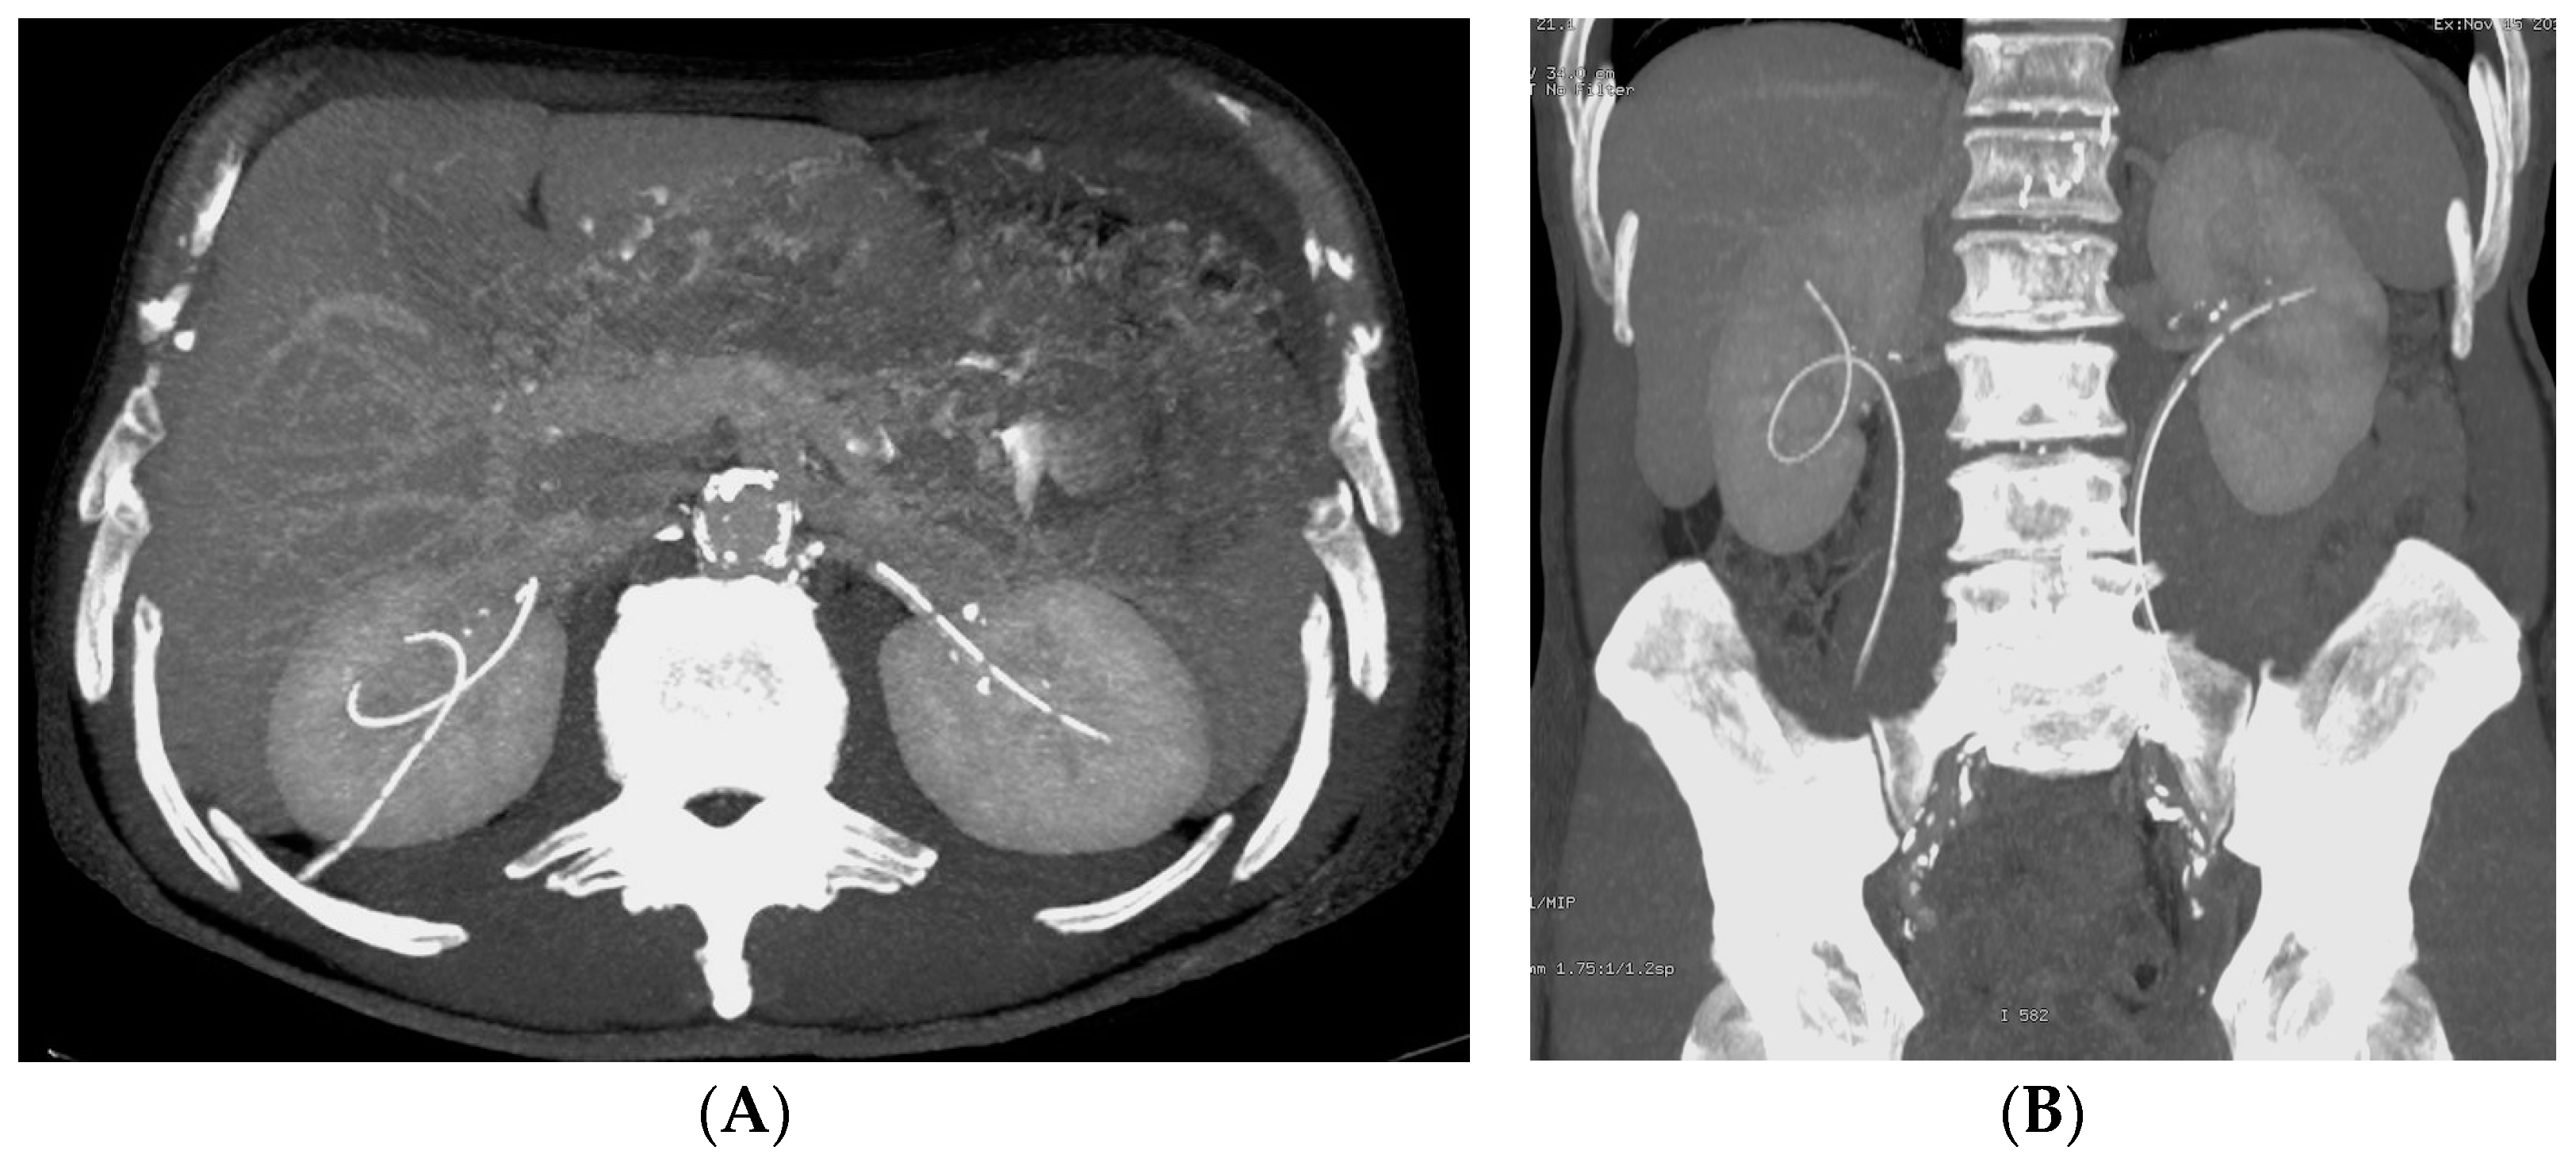

- Urinary tract infection: Stent colonization by bacteria, with an overall incidence ranging from 42% to 90%, is a significant clinical challenge that can lead to a urinary tract infection. In some instances, this infection can result in complications, such as acute pyelonephritis (Figure 8) and renal failure [31,32]. For most patients experiencing a ureteral obstruction, stent placement is carried out with antibiotic prophylaxis, typically administered as a single dose concurrent with the procedure. In cases where a urinary tract infection is already known, the insertion of the stent should be delayed whenever possible until the appropriate treatment with culture-specific antibiotics allows for urine sterilization [32]. US serves as the first-line diagnostic tool to assess the urinary tract in patients presenting with the symptoms of pyelonephritis. Unfortunately, pyelonephritis lacks clear gray-scale findings useful during characterization [33]. Consequently, most patients with clinically suspected pyelonephritis have negative results from US. In cases where imaging is deemed necessary, CT emerges as the preferred modality, providing comprehensive anatomical and physiological information and accurately delineating both intra- and extra-renal pathological conditions. The presence of urinary tract gas, calculi, hemorrhage, renal enlargement, inflammatory masses, and obstruction can be easily detected by CT. Specifically, the affected regions may show a lower attenuation due to edema with pockets of higher attenuation representing the foci of hemorrhage. However, these findings are frequently absent, and unenhanced CT images may appear normal. It is only after the administration of contrast material that the diagnostic features of pyelonephritis become evident. In advanced stages, sepsis is a potential complication, occasionally presenting a critical issue in a debilitated cancer patient. The close monitoring of the patients after the procedure is imperative, with a heightened awareness of the potential for sepsis. The incidence of sepsis following catheter insertion varies between 1.5% and 7%, particularly in patients with pyelonephritis [1,2].